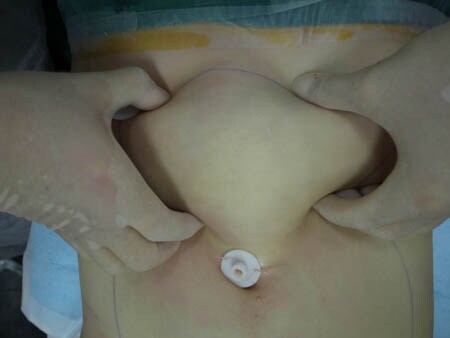

いつものように3Dタッチビュー(超音波)で

皮下脂肪層を評価してみましょう。

上腹部

上の画像の部分の皮下脂肪層をつまんでみましょう。